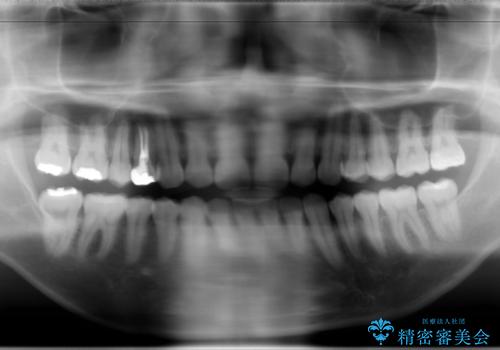

フルリンガル矯正 非抜歯でガタつきを整える

- フルリンガルワイヤーによる非抜歯治療を計画しました。